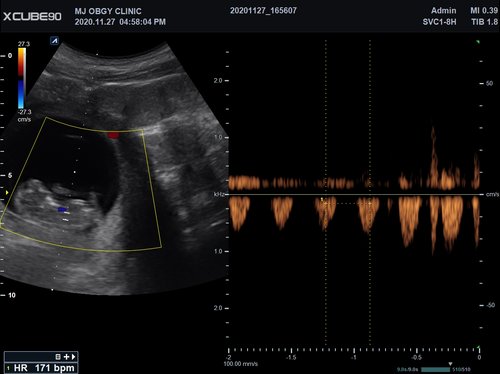

Mit dem X-CUBE 90 beginnt ALPINION eine neue Generation an Farbdopplersystemen, die X- CUBE Serie. Mit Bildverarbeitungstechnologien eines Premiumsystems und neuen Breitband- Schallköpfen mit X + Crystal Signature™ Technologie wartet das neue X-CUBE 90 auf.

X + Architecture

Die X + Architecture ist eine erstklassige Imaging-Plattform, die durch die Kombination von X + Crystal Signature™, der Schallkopftechnologie mit hoher Sensitivität und Breitbandigkeit, und X + FIT, ALPINIONs modernste Beamforming- und Datenverarbeitungstechnologiengeschaffen wurde. X + FIT ist eine neue Technologie, die den Schallstrahl scharf fokussiert sendet, ein großes Datenvolumen empfängt und mit hoher Geschwindigkeit verarbeitet. Darüber hinaus nutzt X + Crystal Signature™ Einkristalle und unser eigenes entwickeltes Schallkopfmaterial, um eine hervorragende Brillanz zu erzielen und die Diagnosemöglichkeiten zu erweitern.

eXpanded Capability

Das X-CUBE 90 bietet modernste Technologien für eine objektive und akkurate Diagnose. Intelligente klinische Module heben das System auf ein neues diagnostisches Niveau. Es erweitert Ihre Fähigkeiten und die Bandbreite Ihrer Möglichkeiten. Dazu gehören Module wie MicroView, point Shear Wave Elastographie (pSWE), oder auch die Kontrastmittelsonographie.